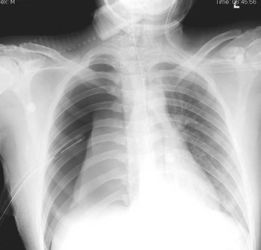

胸透可以看到胸部的軟組織、骨骼(包括胸椎)、縱隔(心臟、大血管、氣管、食管等)、氣管和支氣、胸膜、肺組織等??梢栽\斷肺和氣管的先天性疾病,如發(fā)育異常、肺部的各種炎癥、急慢性支氣管炎、比較明顯的支氣管擴張癥、肺氣腫或肺水腫、各型肺結核、肺腫瘤、胸腔積液、氣胸、縱隔腫瘤、心臟形態(tài)異常等

健康查體最常做的是胸部的X線檢查,最基本的就是胸透。 胸透可以看到胸部的軟組織、骨骼(包括胸椎)、縱隔(心臟、大血管、氣管、食管等)、氣管和支氣、胸膜、肺組織等。

可以診斷肺和氣管的先天性疾病,如發(fā)育異常、肺部的各種炎癥、急慢性支氣管炎、比較明顯的支氣管擴張癥、肺氣腫或肺水腫、各型肺結核、肺腫瘤、胸腔積液、氣胸、縱隔腫瘤、心臟形態(tài)異常等。